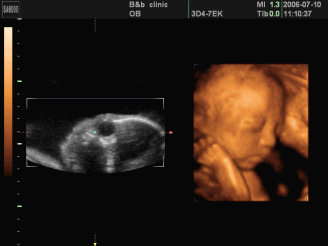

三维彩超是在二维超声的基础上,利用计算机再处理技术达到立体模式重建的超声诊断技术,能看到胎儿的立体图形。

四维彩超就像摄像机拍摄的VCR,在三维B超的基础上加上了时间轴,就像是摄像机所拍摄到的画面,是动态的宝宝。所以才会出现人们所说的可以看到胎儿在体内打哈欠的全过程的情况。

三维彩超、四维彩超的图像则是后期生成的,并不是说观察到的图像就是三维、四维的,而是仍然用普通彩超观察,然后通过仪器中的转换软件将观察到的平面图像转成三维、四维的立体图像。